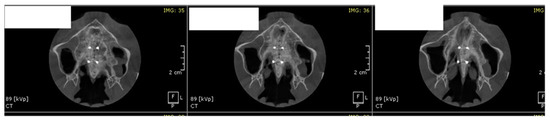

Surgical Protocol

- MARPE associated with cortico-puncture therapy efficiently split the midpalatal suture in adults. The mean split at the anterior nasal spine (ANS) and posterior nasal spine (PNS) was 3.76 and 3.12 mm, respectively. The magnitude of the split at the PNS was smaller than at the ANS (by approximately 85% of the distance), showing that the opening of the midpalatal suture was almost parallel in the anteroposterior direction.

- Our results suggest that non-surgical palatal expansion, assisted by micro-implants and cortico-puncture, is achievable and predictable in young adults. This occurs in safe conditions without the need for more complex surgical treatment.

- The combination of MARPE and the cortico-puncture method proved to be a non-surgical treatment option to correct maxillary transverse deficiency in young adult patients. Cortico-puncture was able to weaken the suture interdigitation, thus facilitating the split.